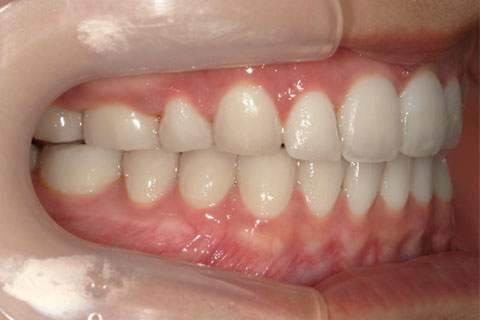

主訴:隙間が気になる

診断名:上顎正中離開

症状:上顎正中離開

患者プロフィール:北九州市・小倉北区30代女性

治療方針:非抜歯矯正治療

治療装置:マウスピース型矯正治療(インビザライン)

抜歯:無し

治療期間:8か月

通院回数:12回

リテーナー: 上顎プレートタイプリテーナー 下顎フィクスタイプリテーナー

治療費用:検査診断料(20,000)+装置料金(500,000)+管理調整料(40,000) +装置撤去時診断料(10,000) +保定装置料金(20,000)=580,000(消費税込)

リスク副作用:痛み・治療後の後戻り・歯根吸収・歯髄壊死

詳しい症例説明: この患者さんは隙間が空いていることを気にされて来院されました。マウスピースタイプの矯正装置で短期間で治療を終えることができました。インビザライン(マウスピース矯正治療)で矯正治療を行うことで治療中も快適に生活できたとのことです。